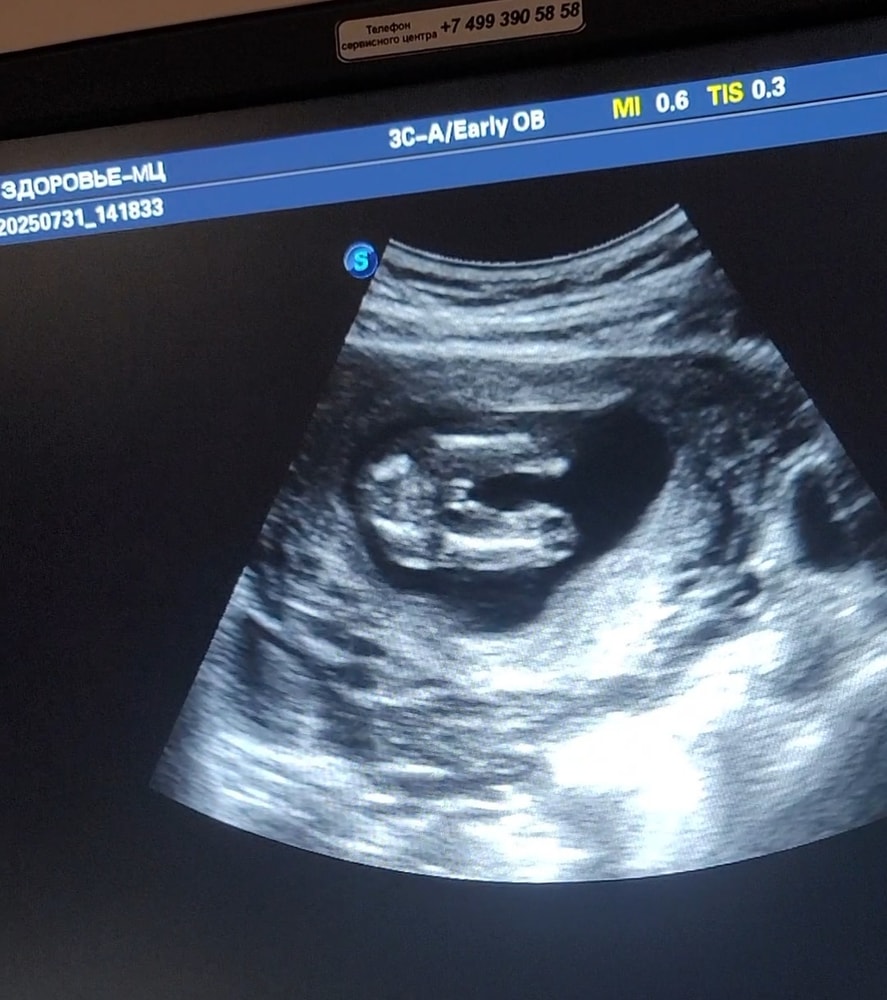

Автор, у Вас прям как у меня. Мне в 13,19, 21, неделю говорили 100% девочка. Пол не показывали, так как был гендер пати. А в 37 недель врач по узи говорит больше похоже на мальчика, машонка и пиптик вверх торчит. Нам уже всё равно какой пол, только я фанатею от розового🤗, много вещей в этих цветах. Ждём сюрприза при рождении😊. Вот такая у нас картина с полом в 37 недель.

Анастасия, я по узи не вижу девчачье, там выражено видно машонка и писюн вверх торчит. Пирожка и близко нет, по крайне мере у моих девочек такого не было, там явный был пирожок и писюн не торчал. Я больше поверю узи на поздних сроках чем на не больших.

Анастасия, сразу обрезанная с двух сторон пуповина? Сама врач сказала на узи что на писюн похоже, девочка маловероятно, но не исключает, пуповина толще на таких сроках. Я ещё раз пишу что доверяю узи на поздних сроках, когда яйца опускаются в мошонку и видно что пацан, на 20 неделях яйца в машонку ещё не опускаются и легко принять пустую машонку за половые губы, ещё когда писюнчик вверх смотрит, и могут его не заметить. Поэтому заказала немного мальчуковых вещей, чтоб розовыми не позорится на случай сюрприза. Девочке синий цвет подайдёт, а мальчику розовое это пипец будет, избавьте меня от этого. Нейтральные оттенки есть, но мне нравятся синие и розовое на детка новорождённых.